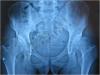

陈晓东教授提供—双侧髋臼发育不良

患者,男性,22 岁。双侧髋臼发育不良。长时间行走后,右侧髋部出现疼痛。接受髋臼周围截骨手术后,髋臼对股骨头的覆盖恢复正常。